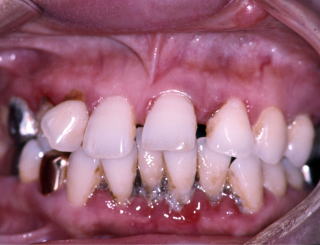

(図1)初診時(1975年10月15日)、38歳。歯肉出血が主訴で紹介された。当時、歯周疾患治治療は一部の臨床家以外はあまり関心が払われていなかった

(図2)初診時(1975年10月15日)、38歳。まず徹底的なPlaque Controlから始めた